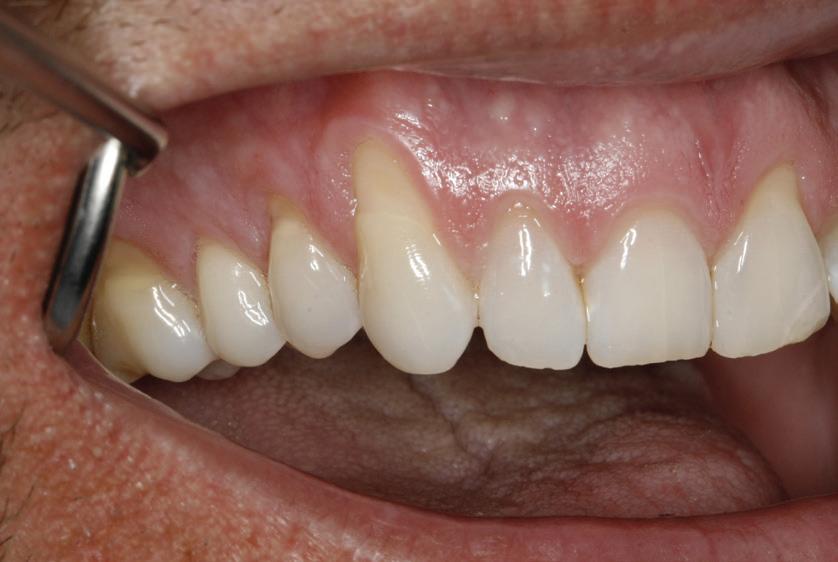

• Pacient cu restaurări deficitare pe dinți compromiși structural, tratamente endodontice eșuate, mobilitate avansată, pungi parodontale profunde, incisiv lateral absent congenital restaurat prin substituție canină inestetică, linie înaltă a zâmbetului. Rezolvarea? Colaborarea cu endodont, parodontolog, ortodont, protetician. Rezultatul? Succes clinic și satisfacția pacientului.

• Chirurgia implantară cu cea mai inteligentă planificare și mai precisă execuție va necesita în continuare un finisaj protetic care funcționează biomecanic și realizează o estetică naturală ideală individuală. Dacă există un aspect al tratamentului protetic cu provocări în era digitală, acesta ar consta în munca artistică minuțioasă a ceramistului, cu modelarea și pictarea dinților pentru a imita natura.

Colaborarea profesională și planificarea ghidată protetic sunt esențiale pentru rezultate predictibile de succes.